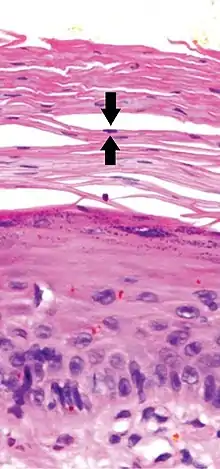

Early actinic keratosis with parakeratosis, with black arrows indicating one of multiple retained nuclei in the stratum corneum

Parakeratosis is a mode of keratinization characterized by the retention of nuclei in the stratum corneum.[1] In mucous membranes, parakeratosis is normal.[2] In the skin, this process leads to the abnormal replacement of annular squames with nucleated cells. Parakeratosis is associated with the thinning or loss of the granular layer and is usually seen in diseases of increased cell turnover, whether inflammatory or neoplastic. Parakeratosis is seen in the plaques of psoriasis and in dandruff.